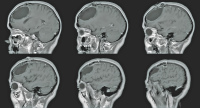

Fallbericht: Blickdiagnose "Arachnoidalzyste" erweist sich als Irrtum: akute Symptomatik einer 14 Jahre alten supratentoriellen endodermalen Zyste

Journal für Neurologie, Neurochirurgie und Psychiatrie 2015; 16 (4): 178-182 Volltext (PDF) Praxisrelevanz Abbildungen